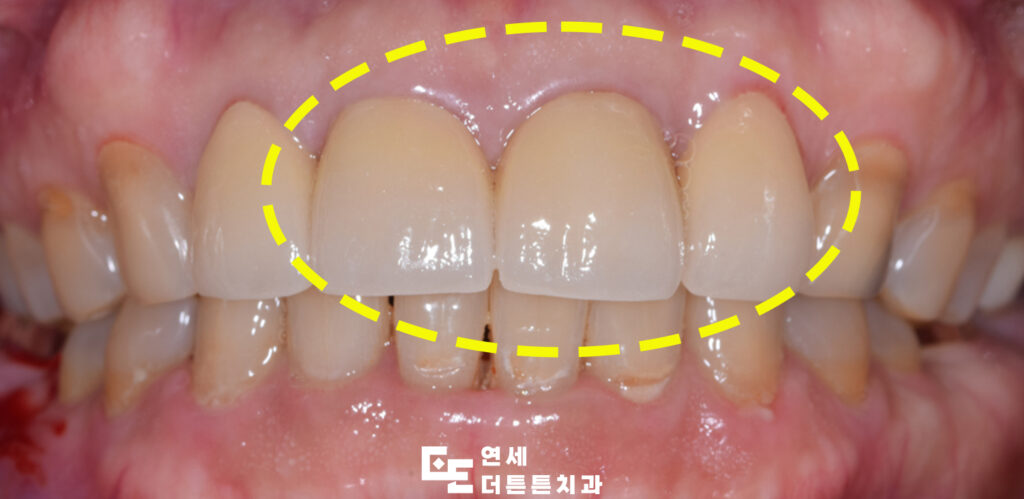

앞니 크라운을 마친 모습인데요.

또한 방학역치과 앞니 크라운 치료의 장점은 다소 삐뚤삐뚤한 치아도 크라운 치료를 통해 가지런하게 만들 수 있다는 점으로 보통 앞니가 삐뚤삐뚤한 경우 교정 치료를 하게 되는데 크라운을 해야 하는 상황에 놓여 있다면 교정 치료 없이 빠르게 가지런한 치아를 가질 수 있게 되는 것이 장점입니다. 또한, 다양한 재료들이 존재하는데 크게는 금과 지르코니아, 세라믹 등으로 나뉘어져 있으며 앞니는 보이는 치아이기 때문에 치아 색과 유사하거나 혹은 더 밝은 색으로도 제작이 가능한 세라믹이나 지르코니아 등의 재료를 사용하게 됩니다.